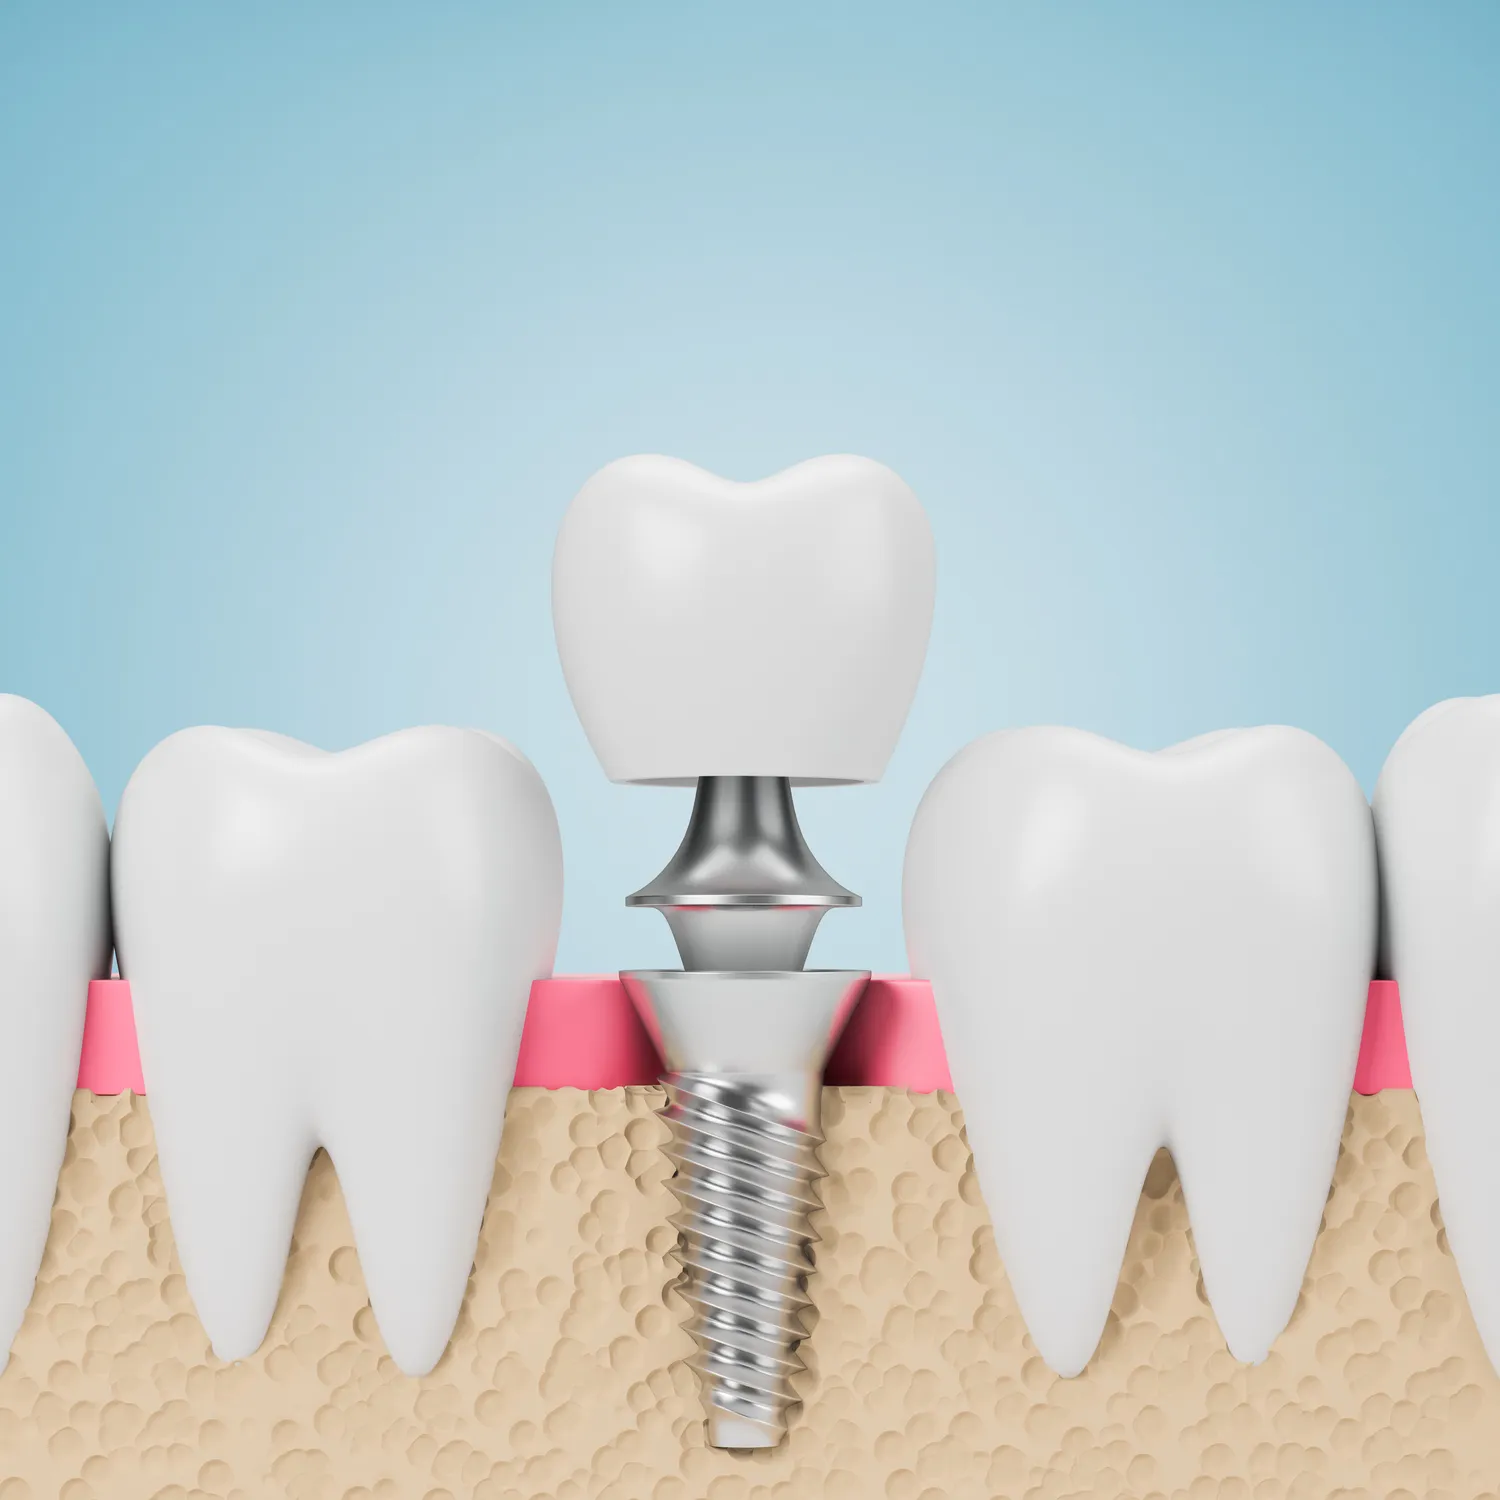

Implant zęba to sztuczny korzeń, który jest wszczepiany w kość szczęki w celu zastąpienia brakującego zęba. Składa się zazwyczaj z tytanu, materiału biokompatybilnego, który dobrze integruje się z kością. Proces wszczepienia implantu rozpoczyna się od dokładnej oceny stanu zdrowia pacjenta oraz przeprowadzenia zdjęć rentgenowskich, które pozwalają lekarzowi ocenić gęstość kości i zaplanować zabieg. Po umieszczeniu implantu w kości następuje proces osteointegracji, który trwa kilka miesięcy. W tym czasie implant łączy się z kością, co zapewnia stabilność i trwałość całej konstrukcji. Po zakończeniu tego etapu na implancie umieszczana jest korona, która ma na celu przywrócenie funkcji i estetyki uśmiechu.

Proces leczenia implantologicznego składa się z kilku etapów, które są starannie zaplanowane przez specjalistę. Pierwszym krokiem jest konsultacja stomatologiczna oraz diagnostyka obrazowa, która pozwala ocenić stan kości oraz określić najlepszą lokalizację dla implantu. Następnie przeprowadzany jest zabieg chirurgiczny polegający na wszczepieniu implantu do kości szczęki. Po tym etapie następuje okres gojenia trwający zazwyczaj od kilku tygodni do kilku miesięcy, podczas którego implant integruje się z kością. Po zakończeniu tego procesu lekarz wykonuje kolejne kroki związane z przygotowaniem korony protetycznej oraz jej osadzeniem na implancie. Warto pamiętać o regularnych wizytach kontrolnych u dentysty po zakończeniu leczenia, aby monitorować stan implantu oraz zdrowie jamy ustnej pacjenta.